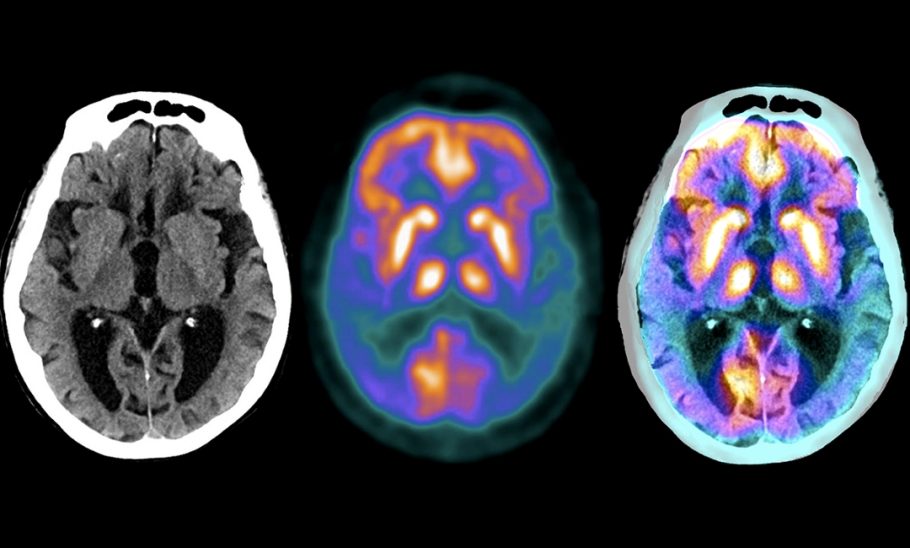

بەپێی هەواڵێکی ScienceDaily مێشکمان خانەی بەرگری تایبەتی هەیە کە پێی دەوترێت مایکرۆگلیا (microglia). وەک تیمێکی پاککەرەوە، ئەم خانانە ئەرکی پاککردنەوەی پاشماوەیان لەسەرە، لەنێویاندا پلاکی پڕۆتینی زیانبەخش. بەڵام توێژینەوە نوێیەکان دەریدەخەن کاتێک مایکرۆگلیا لە پلاکی ئامیلۆید نزیک دەبێتەوە، شتێک بەسەریاندا دێت و دەست دەکەن بە کۆکردنەوەی بڕێکی زۆر چەوری.

ئەم خانە بەرگریانە کە بەهۆی چەورییەوە خنکێنراون، بە شێوەیەکی کاریگەر ئیفلیج دەبن. توانای پاککردنەوەی پلاکەکانیان لەدەست دەدەن و لەبری ئەوەی سەربازی هێڵی پێشەوەی مێشک بن، دەبنە خانەیەکی بێکاریگەر و ئیفلیج.

ئەم کەڵەکەبوونە دەبێتە هۆی ئەوەی مایکرۆگلیا بەردەوام ترشە چەوریەکان بگۆڕێت بۆ چەوری هەڵگیراو، نەک بەکاریبهێنێت بۆ وزە و بەرەنگاربوونەوەی نەخۆشی، تاوەکو بە تەواوی تێر دەبن بەم کۆگا چەورییانە و بێ جووڵە دەبن.